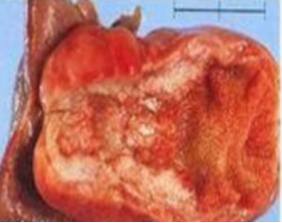

綜上所述,膽囊結(jié)石與膽囊癌關(guān)系密切,是誘發(fā)膽囊癌的重要危險(xiǎn)因素。研究表明膽囊癌合并膽囊結(jié)石高達(dá)70%,膽囊結(jié)石誘發(fā)膽囊癌的危險(xiǎn)性是非結(jié)石患者的4-5倍。因此對(duì)于靜止期膽囊結(jié)石大家可以繼續(xù)動(dòng)態(tài)觀察外,合并膽囊炎的結(jié)石建議早期行膽囊切除術(shù)。最后讓我們一起看一下膽囊癌的真實(shí)面目,對(duì)便大家對(duì)它有更直觀的認(rèn)識(shí),引起大家的足夠重視,做到“早發(fā)現(xiàn)、早治療”。